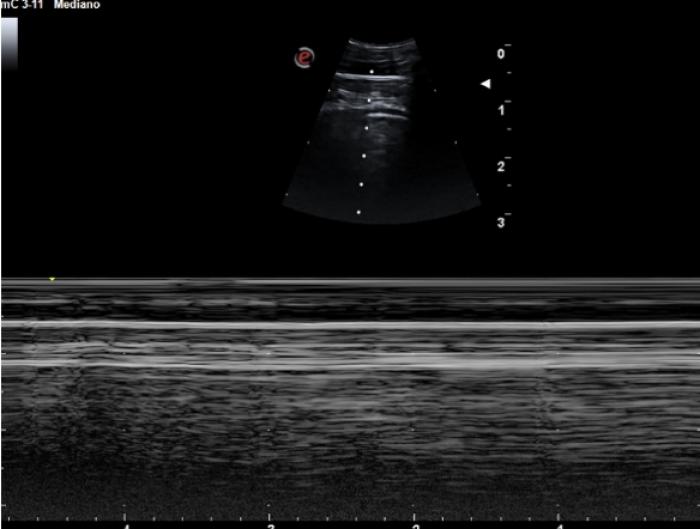

Signo del sinusoide y cuadrilátero

La presencia de pequeñas colecciones de fluido en el espacio pleural no siempre son del todo fáciles de evaluar, especialmente si el contenido en cuestión es lo suficientemente celular como para no visualizarse anecoico. El uso del modo M en estas circunstancias puede ser muy útil. Nos posicionamos con el transductor transversal en el espacio intercostal seleccionado (áreas más declives tienen mayor porcentaje de éxito puesto que el fluido desciende por gravedad), situamos el cursor y activamos el modo M, puesto que el pulmón no está en contacto en todo momento con la pared costal, la LP dibujará un movimiento sinusoidal en el registro en movimiento, muy diferente de la recta hiperecogénica que vemos en el tórax sano (Figura 9A-B).